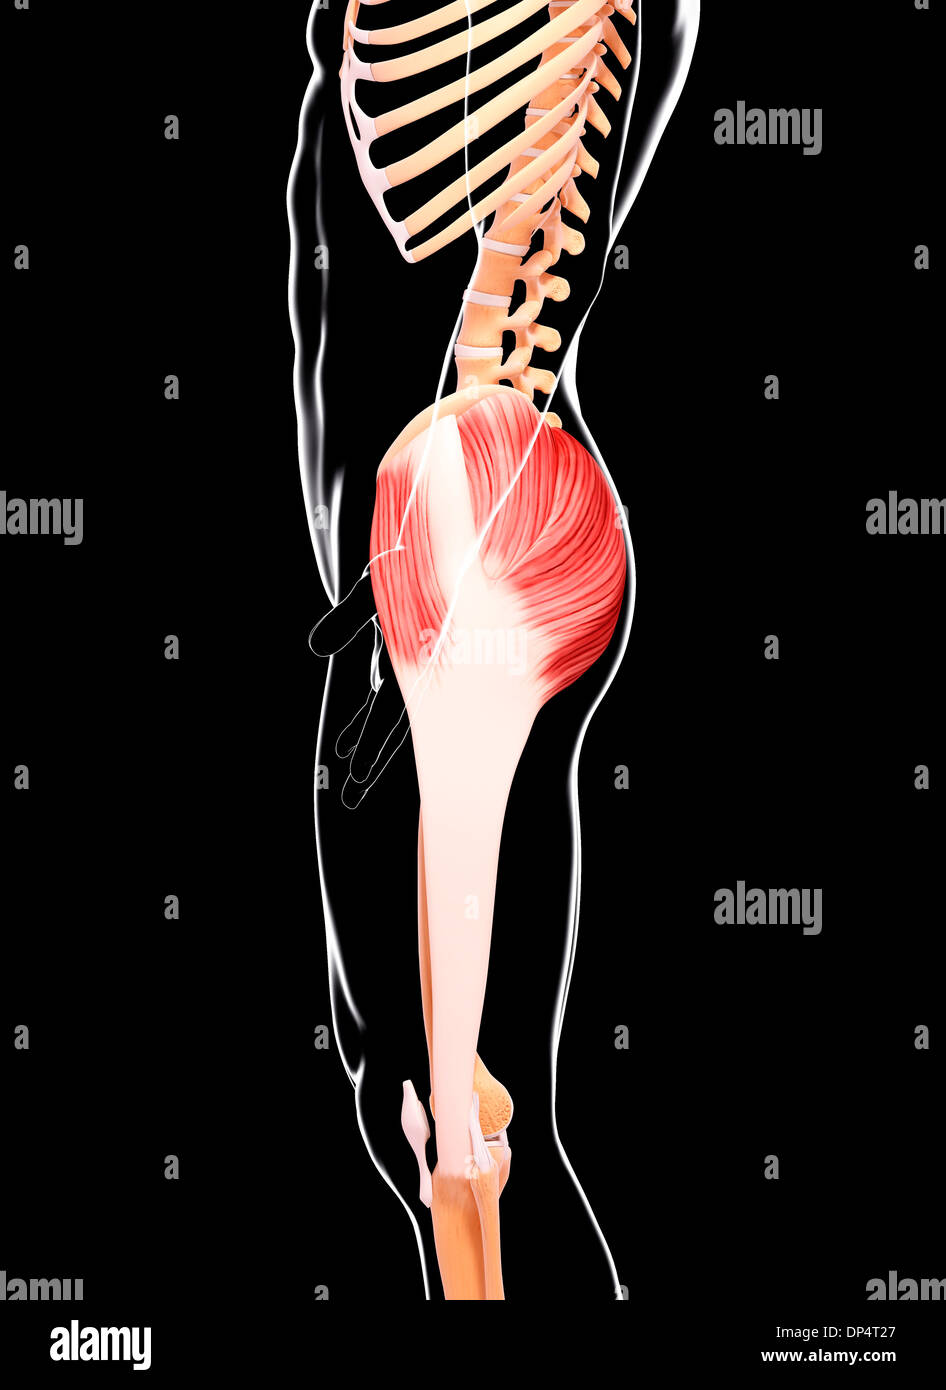

Human musculature, artwork Stock Photohttps://www.alamy.com/image-license-details/?v=1https://www.alamy.com/human-musculature-artwork-image65260223.html

Human musculature, artwork Stock Photohttps://www.alamy.com/image-license-details/?v=1https://www.alamy.com/human-musculature-artwork-image65260223.htmlRFDP4T27–Human musculature, artwork

Human musculature, artwork Stock Photohttps://www.alamy.com/image-license-details/?v=1https://www.alamy.com/human-musculature-artwork-image65257604.html

Human musculature, artwork Stock Photohttps://www.alamy.com/image-license-details/?v=1https://www.alamy.com/human-musculature-artwork-image65257604.htmlRFDP4MMM–Human musculature, artwork